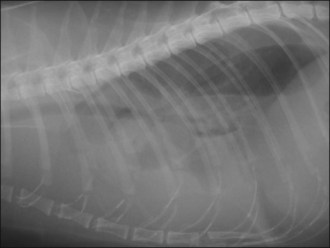

Oxygen supplementation was continued and the cat monitored closely, and she slowly began to show improvement. At the appropriate time, thoracic radiographs were taken under mild sedation (butorphanol 0.2 mg/kg i.v.) and revealed a severe diffuse bronchointerstitial lung pattern (Figure 32.5). A diagnosis of chronic bronchial disease with acute exacerbation was made.

image image

Figure 32.5 (a) Right lateral and (b) dorsoventral thoracic radiographs of a cat showing a severe diffuse bronchointerstitial lung pattern.